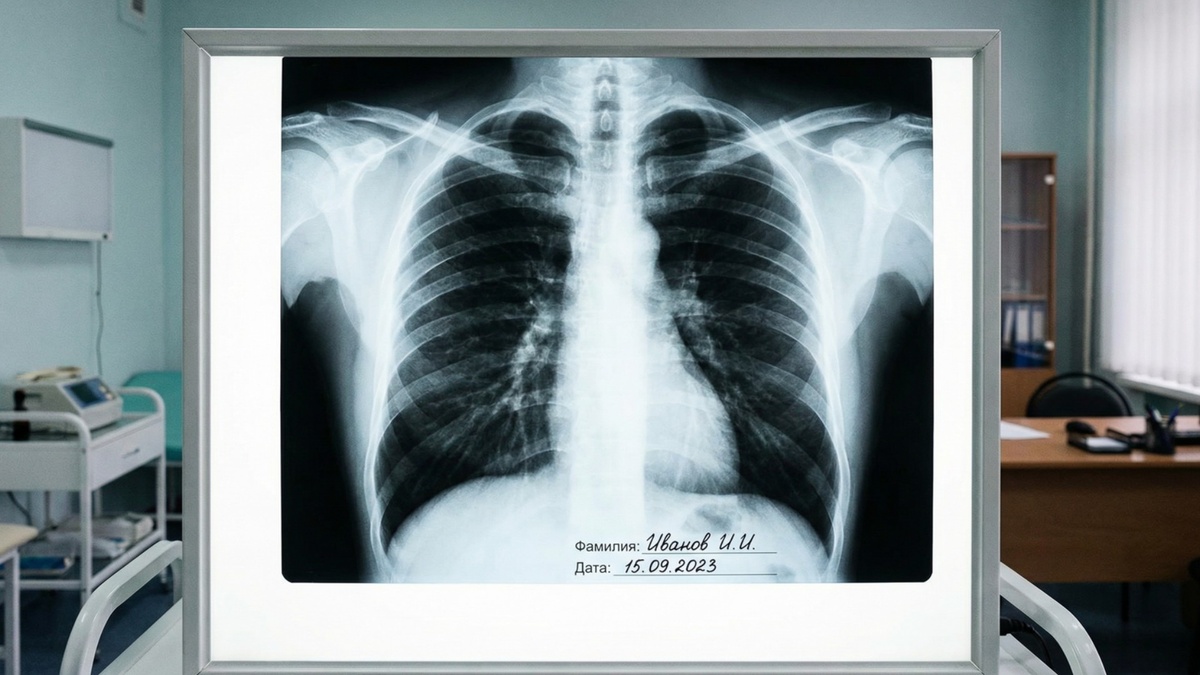

Вейпы также приводят к специфическому поражению легких EVALI — при этой патологии легочные оболочки деформируются, будто человек перенес острую двустороннюю пневмонию. Последствиями ее может стать тяжелая дыхательная недостаточность.